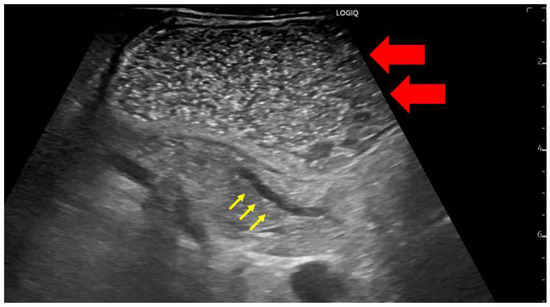

In Japan, most early-stage PDACs were accidentally identified via abdominal ultrasonography at medical checkups or while screening for other diseases [9,10]. TUS is less invasive and widely used; however, the degree of pancreatic imaging in abdominal ultrasonography often depends on the patient’s body shape and gastrointestinal gas status. Furthermore, this technique often makes it challenging to observe the entire pancreas. Patients should be placed in a half-sitting position to observe the entire pancreas via abdominal ultrasonography. This position allows the liver to hang down and be located in front of the pancreas, acting as an acoustic window, thus reducing the influence of intestinal gas. Probe compression may also be applied to patients with a large amount of subcutaneous fat. Additionally, because the pancreas has a relatively large range of motion, postural changes can be actively added. In particular, the visual observation of the pancreas can be improved by taking the right lateral decubitus position for the tail of the pancreas and the left lateral decubitus position for the pancreatic hook. However, the tail of the pancreas is often difficult to visualize because of gastric gas. Thus, drinking 300–700 mL of degassed water would be beneficial (Figure 2).

Figure 2.

A case in which the main pancreatic duct dilatation was observed by using the drinking water method to fill the gastrointestinal tract with liquid for the observation of the pancreatic body tail. The gastrointestinal tract itself can be used as an acoustic window by instructing the patient to drink degassed water (red arrow); this enables the clear visualization of the tail of the pancreas (yellow arrow).